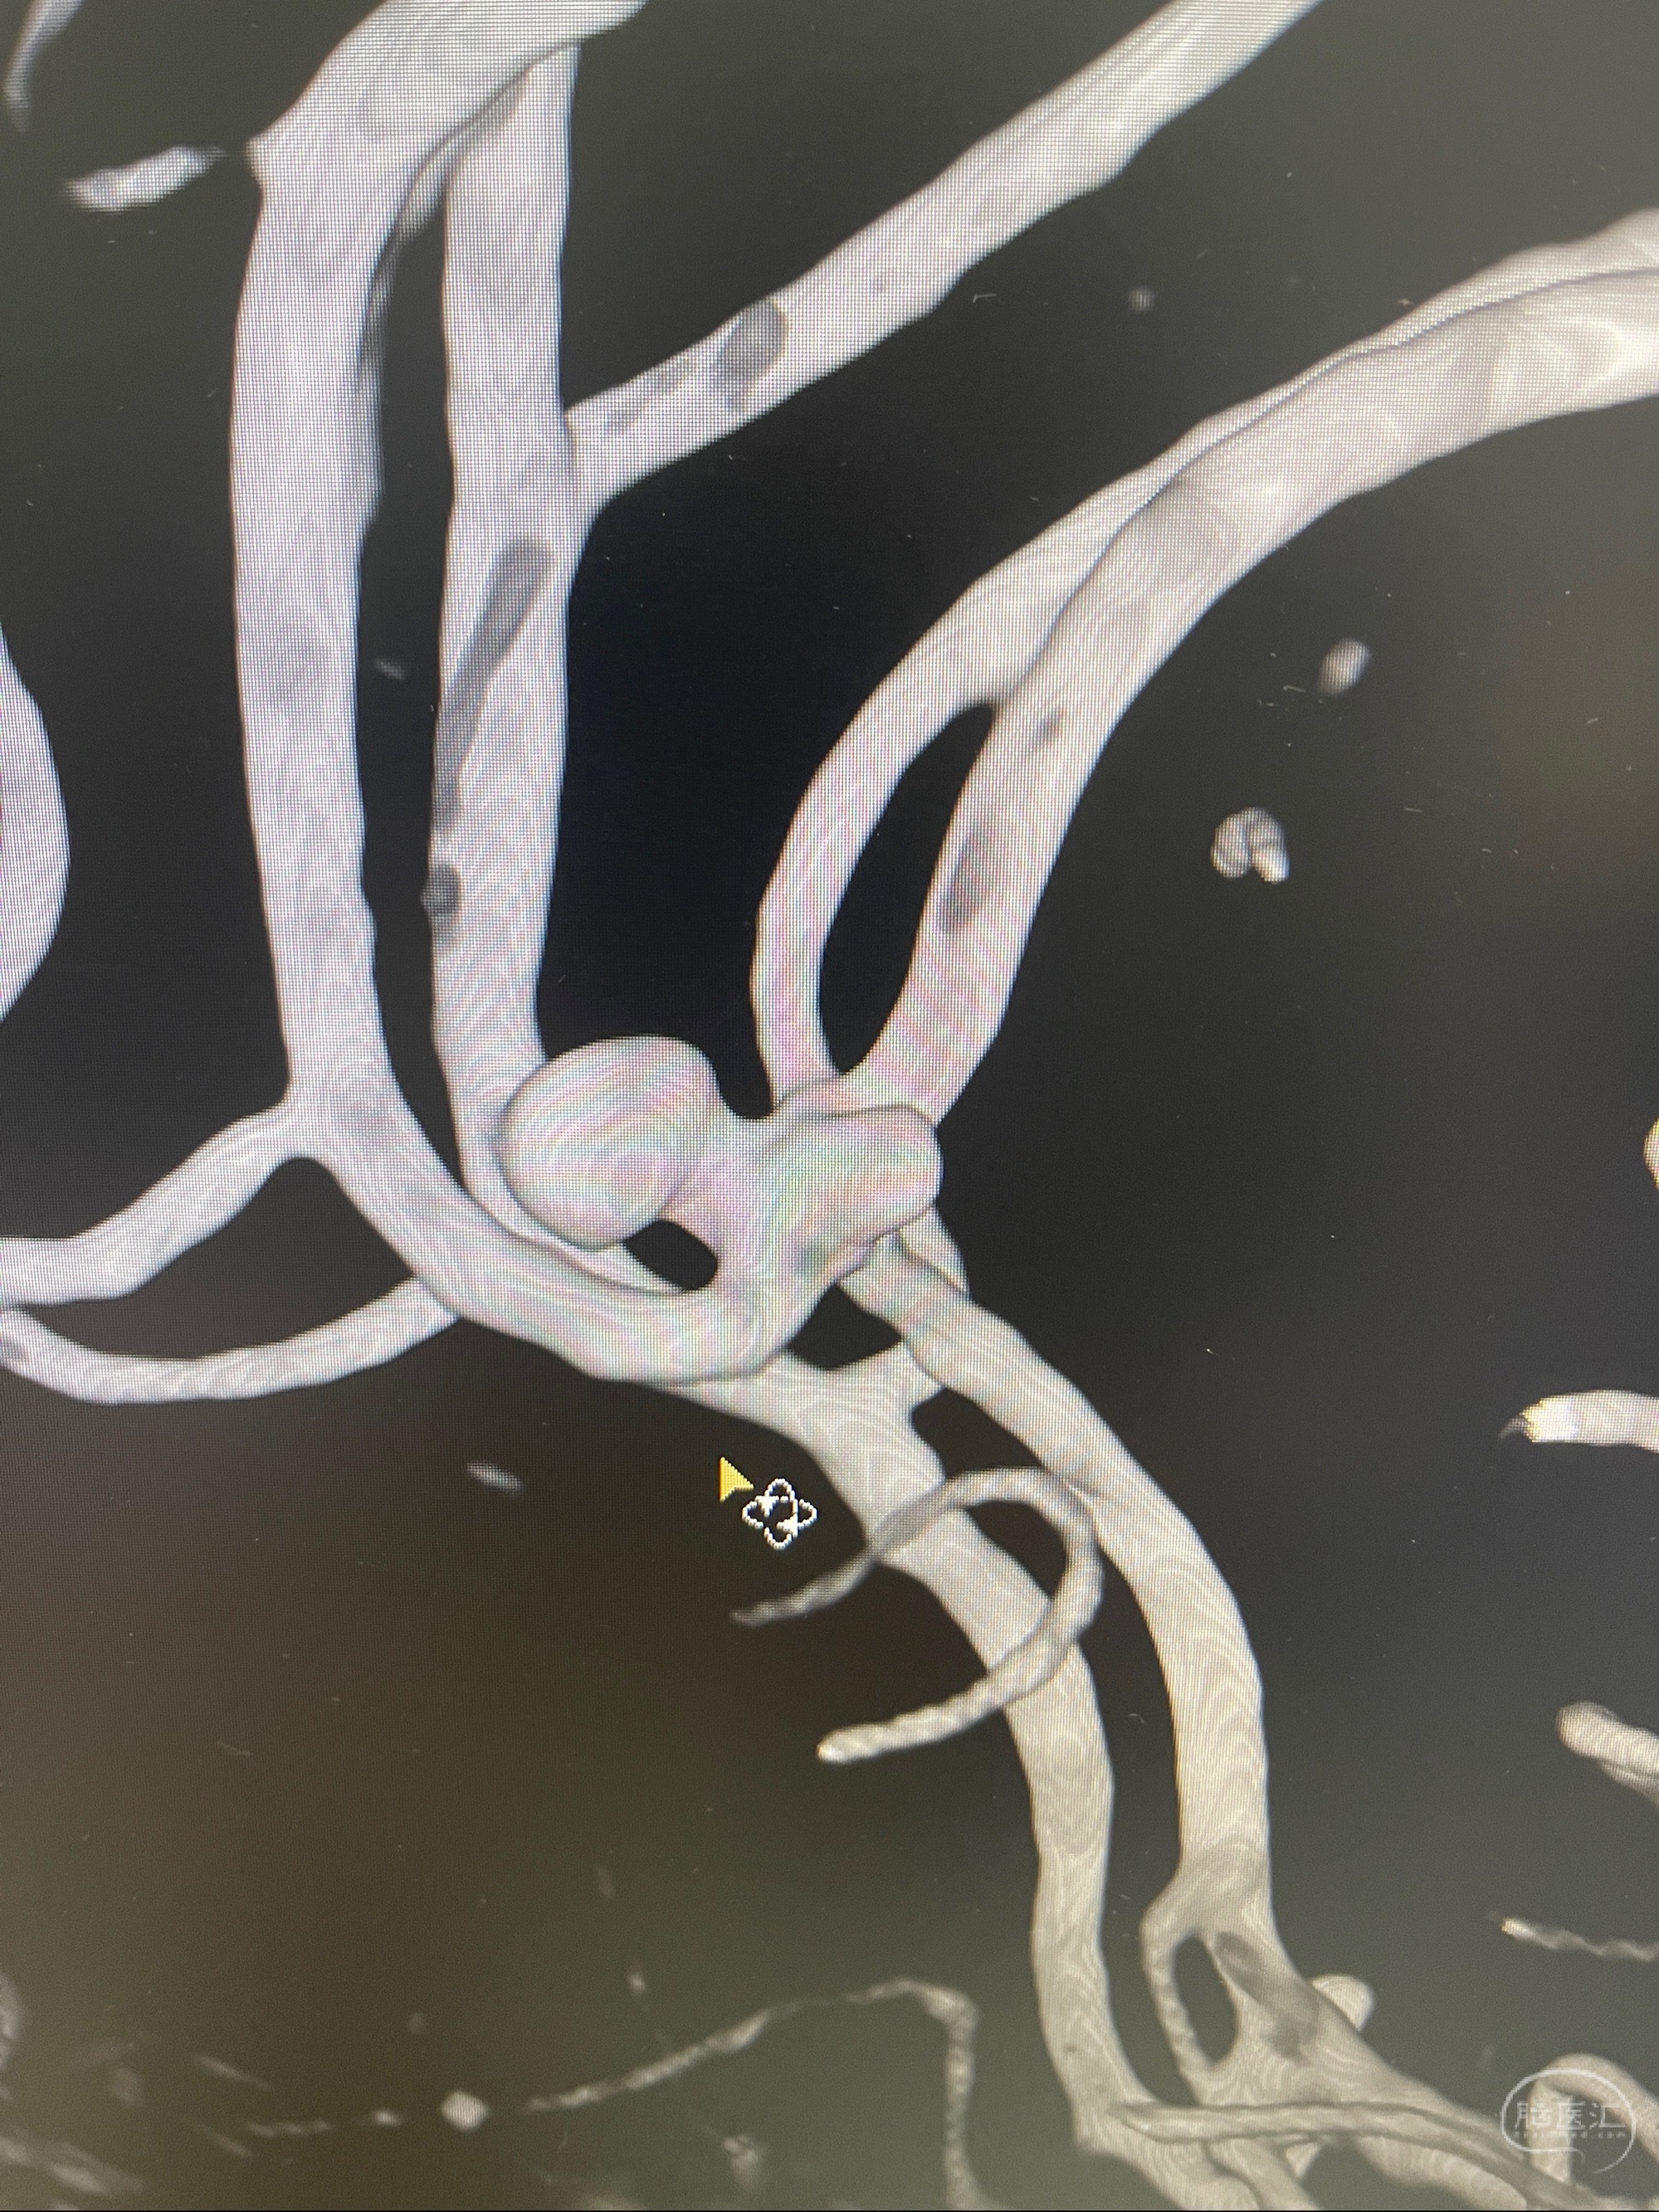

1.左侧大脑前动脉远侧段(A2-A5)动脉瘤

2023-08-23DSA:左侧前交通动脉瘤,左侧A3/4交界处多发动脉瘤